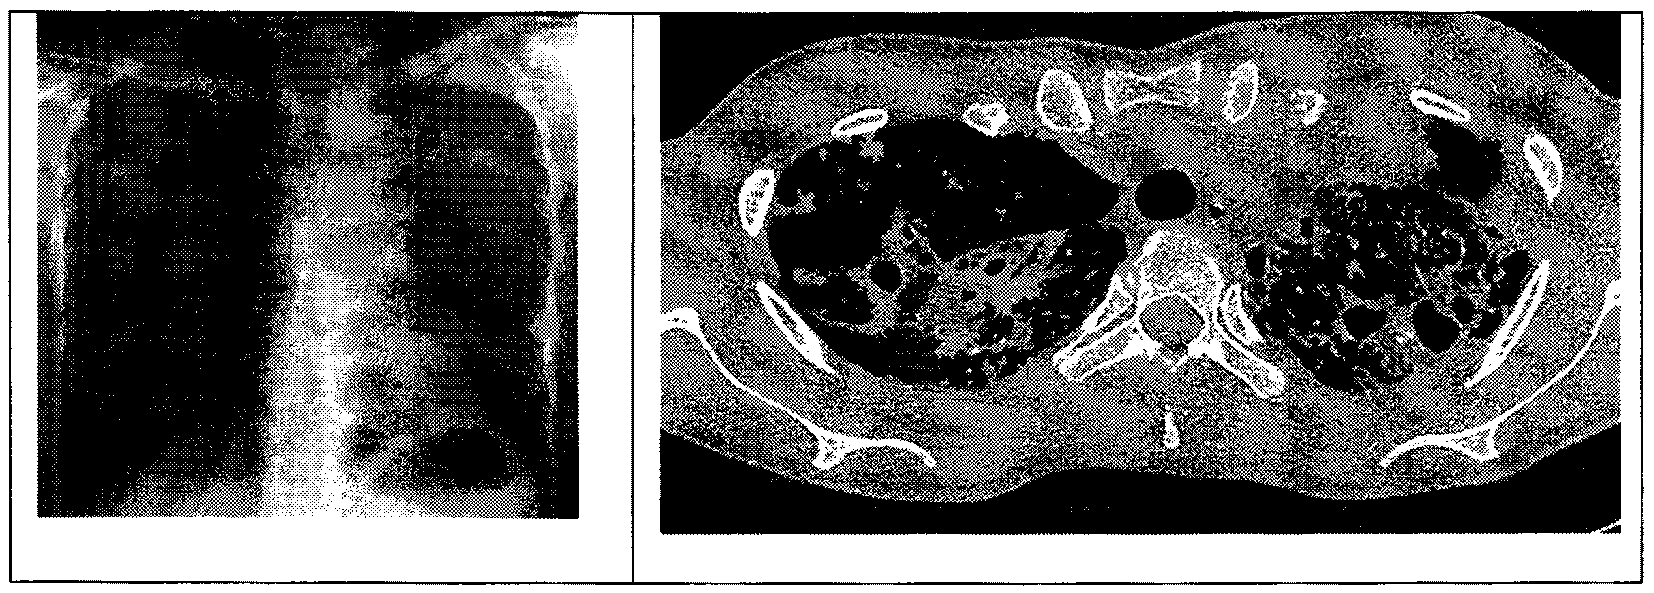

Ситуационная задача 1. Мужчина 77 лет. Доставлен в приемный покой бригадой скорой помощи. Жалобы на кашель и периодическое кровохарканье последние 3 дня в виде прожилок алой крови в мокроте. Неделю назад поднялась и в течение недели сохраняется температура 37,5 - 38,0 °C. Не работает, живет один. Последняя флюорография грудной клетки выполнена 5 лет назад - без патологии. С тех пор к врачу не обращался. В стационаре выполнены рентгенография грудной клетки и компьютерная томография легких.

Определите заболевание, которое можно предположить по данным рентгенографии и рентгеновской компьютерной томографии. Напишите протокол исследования по представленным копиям снимков.

Б. тромбоэмболия легочной артерии;